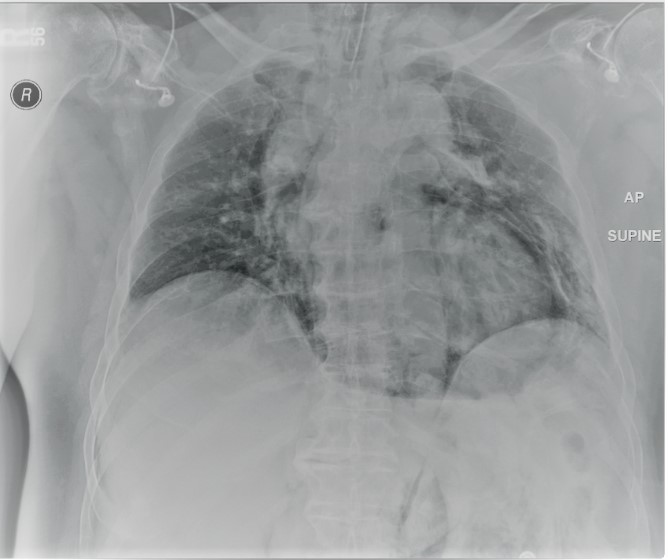

Figure 1. Esophagogram showing a dilated esophagus and bird’s beak deformity.

A 72-year-old gentleman with achalasia who weighed 91 kg was admitted for an elective POEM procedure (Figure 1). The procedure started with stable hemodynamics on a constant ventilator setting of respiratory rate of 10-16/hr; tidal volume of 443; positive end-expiratory pressure (PEEP) of 5 cm H2O; positive inspiratory pressure of 22-24; end tidal carbon dioxide of 28; arterial oxygen saturation of 100. However, 45 minutes into the procedure, the patient went into pulseless electrical arrest. The scope was withdrawn, and he was revived after 10 minutes of cardiopulmonary resuscitation. The procedure was aborted and he was transferred to the ICU intubated, critically ill, and on escalating doses of epinephrine and norepinephrine. Follow-up diagnostic imaging (Figures 2 and 3) showed a small heart with air tracking around it, the mediastinum, the esophagus, and the aorta, confirming tension pneumomediastinum.